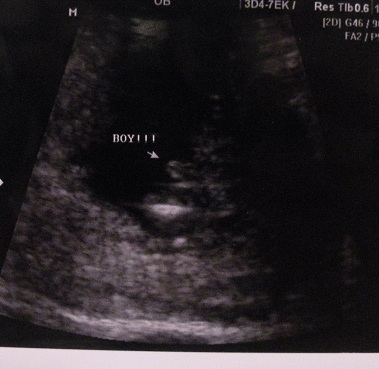

I just had an u/s done when I was 15w2d, where the tech told us we were having a boy. I was truly shocked bc according to Ramzi method baby came up girl (implanted on left side), the HB has always been high (at 8 wks was 150something, 12 wks it was 171, & is now 158-160), other OWT's/tests came out girl, plus my gut feeling said girl & I've not been wrong in all my pregnancies. Here are the potty shot pics, ANY possible way this could end up a girl?

Attachment 5961